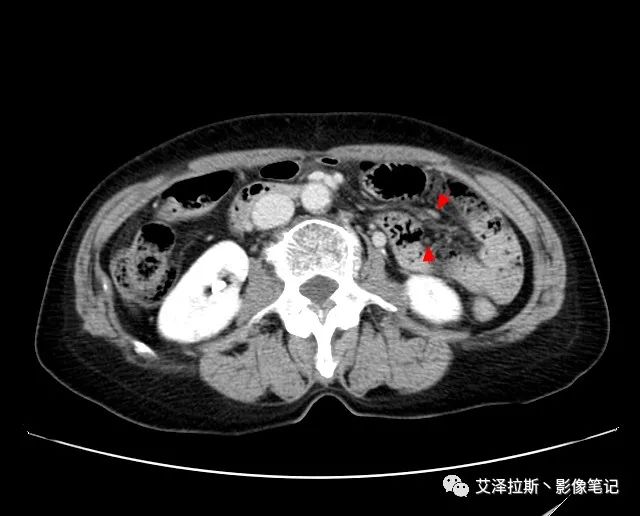

以下為累及的區域淋巴結,共計15個區域:

【影像所見】 胃竇部狹窄,胃壁環形增厚,小彎側見一巨大潰瘍,周圍伴“環堤征”,漿膜面不完整,胃周脂肪見網格狀條索影,病灶與肝臟左葉、胰腺鉤突脂肪間隙消失,增強掃描病灶明顯強化。引流區內約15個區域淋巴結受累。

【診斷意見】 胃竇部胃癌(T4N3期) 該病例腫塊突破漿膜層,與肝臟左葉、胰腺鉤突分界不清,脂肪界面消失,定為T4期; 受累及的淋巴結為15個區域,定為N3; 有無遠處轉移尚不明確,所以M期暫時無法確定。